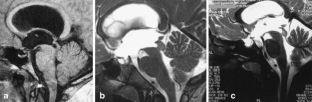

The sylvian aqueduct is the most common site of intraventricular blockage of the cerebro-spinal fluid. Clinical aspects, neuroradiological appearance, and treatment of hydrocephalus secondary to aqueductal stenosis are specific.

The correct interpretation of the modern neuroradiologic techniques may help in selecting adequate treatment between the two main options (third ventriculostomy or shunting). In the last decades, endoscopic third ventriculostomy has become the first-line treatment of aqueductal stenosis; however, some issues, such as the cause of failures in well selected patients, long-term outcome in infant treated with ETV, and effect of persistent ventriculomegaly on neuropsychological developmental, remain unanswered.